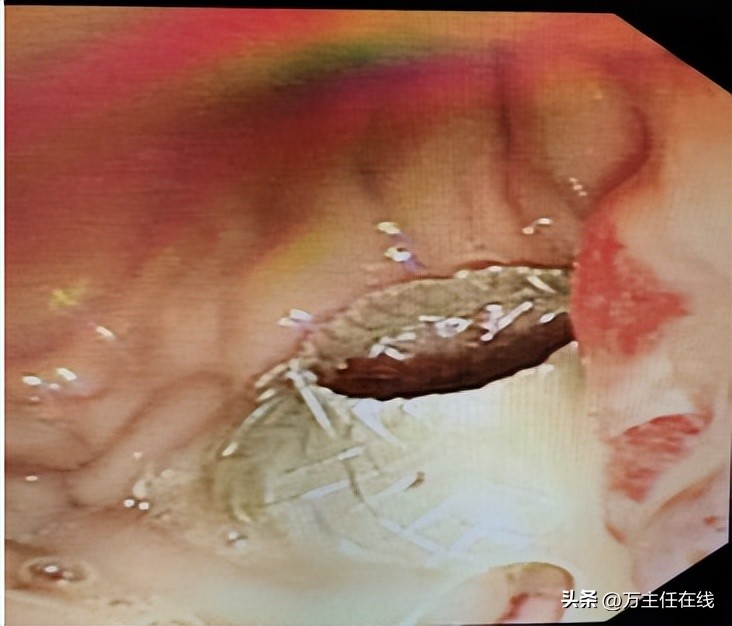

▲ 成功置入AXIOS电切引流一体式支架

手术当日,手术团队先以超声内镜精确定位胰腺尾部约12厘米大小的囊性病灶,用19G穿刺针避开主要血管后穿刺。随着穿刺针刺入,大量棕褐色浑浊囊液涌出,这正是造成患者反复感染的根源。在迅速以X线定位后,手术团队采用新型的“AXIOS电切引流一体式支架”进行后续操作,以减少术中器械交换、降低内瘘及出血风险的同时进行高效引流。万荣教授精准操作内镜及附件逐层切开胃粘膜、囊壁,将支架送入囊腔内。由于患者年幼,胃腔狭小,操作空间十分有限。万荣教授反复尝试最合适的释放位置,最终将支架头端以较特殊的“胃底朝向位”确认后释放。放置完成后,可见胃内金属支架在位、囊液引流通畅。在麻醉科和护理团队的共同努力下,手术用时不到1小时即告完成。